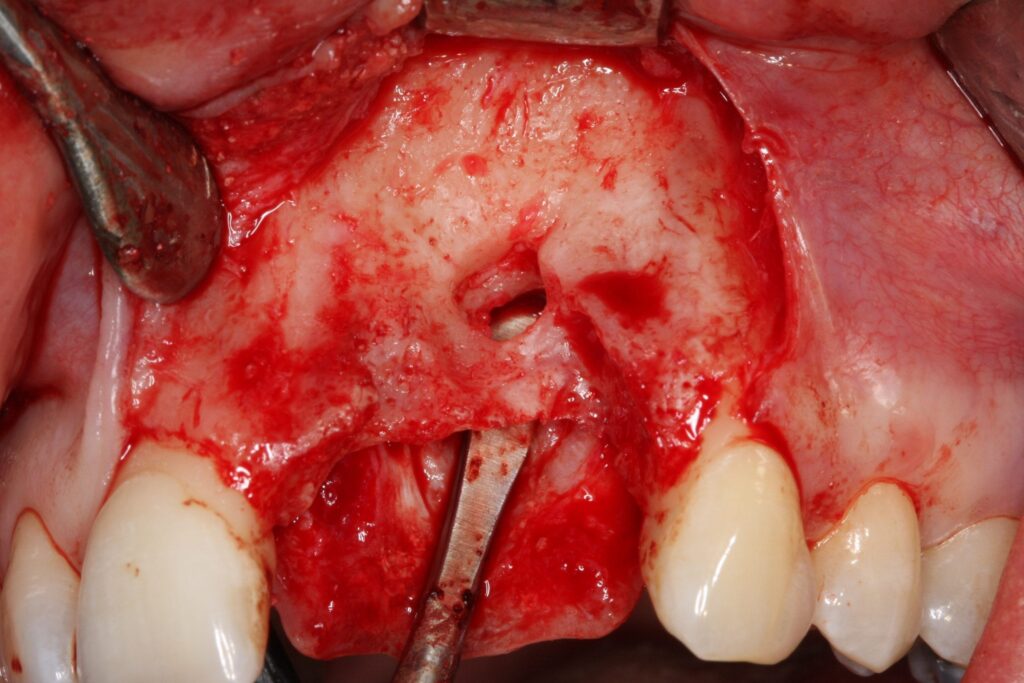

Eine 28-jährige Patientin benötigte Implantat getragenen Zahnersatz, um ihre Zahnlücke im Frontzahngebiet zu schließen und wieder unbeschwert lächeln zu können. Bevor die Implantate gesetzt wurden, war es bei dieser Patientin nötig, den geschädigten Kieferknochen wieder aufzubauen. Im Vorfeld wurde bereits durch Vorbehandler mit Augmentationsversuchen begonnen, welche jedoch leider fehlschlugen. So wurde in mehreren erfolglosen Behandlungsversuchen ein synthetisches Knochenaufbaumaterial verwendet. Dieses führte zu einer ausgedehnten Entzündung in deren Folge statt eines zusätzlichen Knochenvolumens ein massiver Knochendefekt im betroffenen Frontzahngebiet resultierte.

Zunächst einmal mussten die Reste des synthetischen Knochenaufbaumaterials umfangreich entfernt werden. Nur so konnte die Grundlage für einen neuen, nunmehr erfolgreichen, Behandlungsschritt geschaffen werden. Diese Behandlung führte Prof. Dr. Khoury kompetent in unseren Praxisräumen durch. Anschließend konnte mit der Knochenblockaugmentation begonnen werden. Ziel war es, eine stabile und langfristige Grundlage für die Verankerung von Zahnimplantaten zu schaffen.